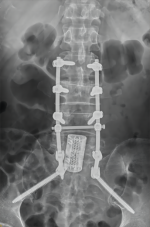

8. 机器人导航辅助下脊柱侧弯矫正技术

脊柱侧弯是一种复杂的脊柱三维畸形,其中以青少年特发性脊柱侧凸最常见。好看视频下载

在浦口地区率先开展机器人导航辅助下脊柱侧弯矫正术,实现了脊柱侧弯手术准确、微创、智能化的突破,获得了良好的效果。还有老年人退变性侧弯,机器人亦可精准置入困难椎弓根螺钉,误差只有0.3mm。